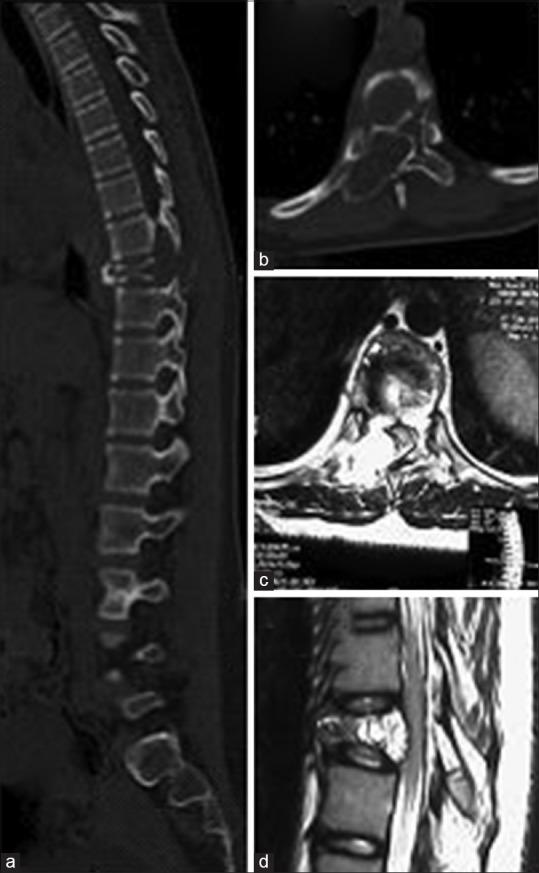

Aneurysmal bone cyst (ABC) is a vascular tumor of the spine. Management of spinal ABC still remains controversial because of its location, vascular nature and incidence of recurrence. In this manuscript, we hereby describe two cases of ABC spine treated by curettage, vertebral cement augmentation for control of bleeding and internal stabilization with two years followup. To the best of our knowledge, this is the first case report in the literature describing the role of cement augmentation in spinal ABC in controlling vascular bleeding in curettage of ABC of spine. Case 1: A 22 year old male patient presented with chronic back pain. On radiological investigation, there were multiple, osteolytic septite lesions at L3 vertebral body without neural compression or instability. Percutaneous transpedicular biopsy of L3 from involved pedicle was done. This was followed by cement augmentation through the uninvolved pedicle. Next, transpedicular complete curettage was done through involved pedicle. Case 2: A 15-year-old female presented with nonradiating back pain and progressive myelopathy. On radiological investigation, there was an osteolytic lesion at D9. At surgery, decompression, pedicle screw-rod fixation and posterolateral fusion from D7 to D11 was done. At D9 level, through normal pedicle cement augmentation was added to provide anterior column support and to control the expected bleeding following curettage. Transpedicular complete curettage was done through the involved pedicle with controlled bleeding at the surgical field. Cement augmentation was providing controlled bleeding at surgical field during curettage, internal stabilization and control of pain. On 2 years followup, pain was relieved and there was a stable spinal segment with well filled cement without any sign of recurrence in computed tomography scan. In selected cases of spinal ABC with single vertebral, single pedicle involvement; cement augmentation of vertebra through normal pedicle has an important role in surgery aimed for curettage of vertebra.

骨动脉瘤样囊肿(ABC)是一种脊柱血管性肿瘤。由于其位置、血管性质和复发率,脊柱ABC的治疗仍存在争议。在本手稿中,我们特此描述了两例经刮除术、椎体骨水泥强化以控制出血并进行内固定治疗的脊柱ABC病例,并进行了两年的随访。据我们所知,这是文献中首例描述骨水泥强化在脊柱ABC刮除术中控制血管出血作用的病例报告。病例1:一名22岁男性患者出现慢性背痛。经影像学检查,L3椎体有多个溶骨性分隔病变,无神经受压或不稳定。对L3受累椎弓根进行了经皮椎弓根穿刺活检。随后通过未受累椎弓根进行骨水泥强化。接下来,通过受累椎弓根进行经椎弓根完全刮除术。病例2:一名15岁女性出现非放射性背痛和进行性脊髓病。经影像学检查,D9有一个溶骨性病变。手术时,进行了减压、椎弓根螺钉-棒固定以及从D7到D11的后外侧融合。在D9水平,通过正常椎弓根添加骨水泥强化以提供前柱支撑并控制刮除术后预期的出血。通过受累椎弓根进行经椎弓根完全刮除术,手术野出血得到控制。骨水泥强化在刮除术、内固定和疼痛控制过程中为手术野提供了出血控制。经过两年随访,疼痛缓解,脊柱节段稳定,骨水泥填充良好,计算机断层扫描未显示任何复发迹象。在选定的单椎体、单椎弓根受累的脊柱ABC病例中,通过正常椎弓根进行椎体骨水泥强化在旨在刮除椎体的手术中具有重要作用。